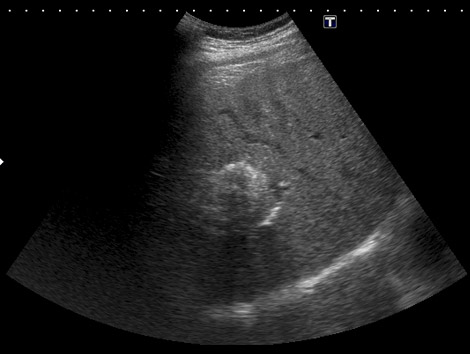

4.2. Quiste hidatídico